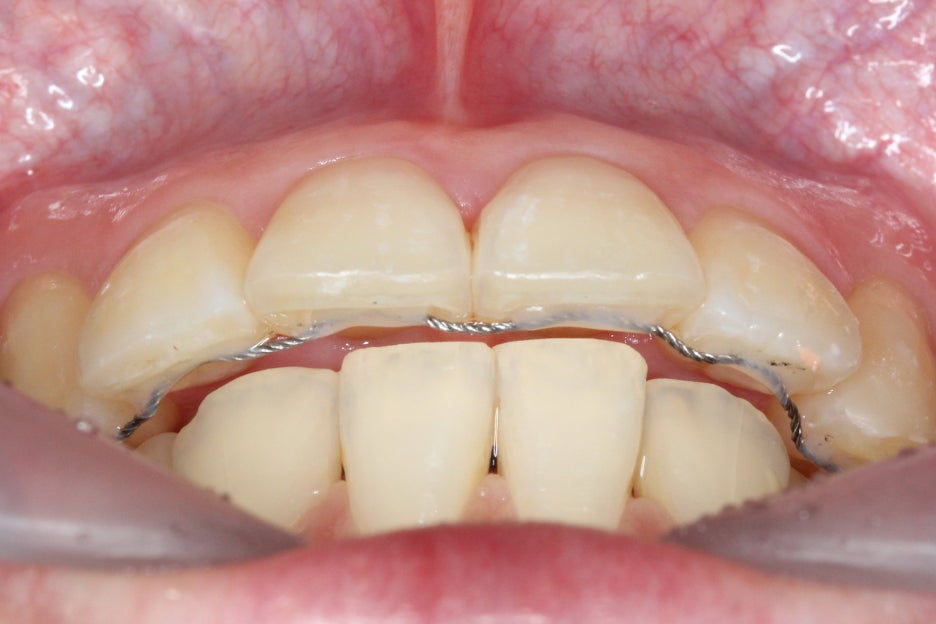

#11, #21 crowding 중심으로

돌출감이 심했던 윗니의

비발치 클리피씨 교정 후

정면 모습입니다.

부분교정으로 상악치열이

초기보다 확연하게

가지런해진 모습인데요,

전치부를 개방했을 때

보이는 치아의 높이도

일정하게 맞추어져서

스마일라인의 심미성이

보완된 모습입니다.

따라서 overbite 사진에서도

중절치의 벌어짐이

상당히 개선된 모습을 확인할 수 있는데요,

비발치로 토끼앞니교정을

진행했기 때문에 발치교정

Case보다는 다소

드라마틱한 변화를

기대하기는 한계가 있습니다.

그러나 문제가 되었던

토끼앞니교정은 치아를

빼고 공간을 만들지 않아도

자연스럽게 해결되었으며,

부분교정으로 상악만

클리피씨 교정을 하였기 때문에

비교적 경제적인 비용으로

단기간에 완성할 수 있었는데요,